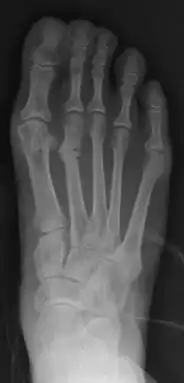

Stress fracture of the second metatarsal bone (below the knuckles of the second toe)

Stress fractures can be described as small cracks in the bone, or hairline fractures. Stress fractures of the foot are sometimes called "march fractures" because of the injury's prevalence among heavily marching soldiers.[2] Stress fractures most frequently occur in weight-bearing bones of the lower extremities, such as the tibia and fibula (bones of the lower leg), metatarsal and navicular bones (bones of the foot). Less common are stress fractures to the femur, pelvis, and sacrum. Treatment usually consists of rest followed by a gradual return to exercise over a period of months.[1]